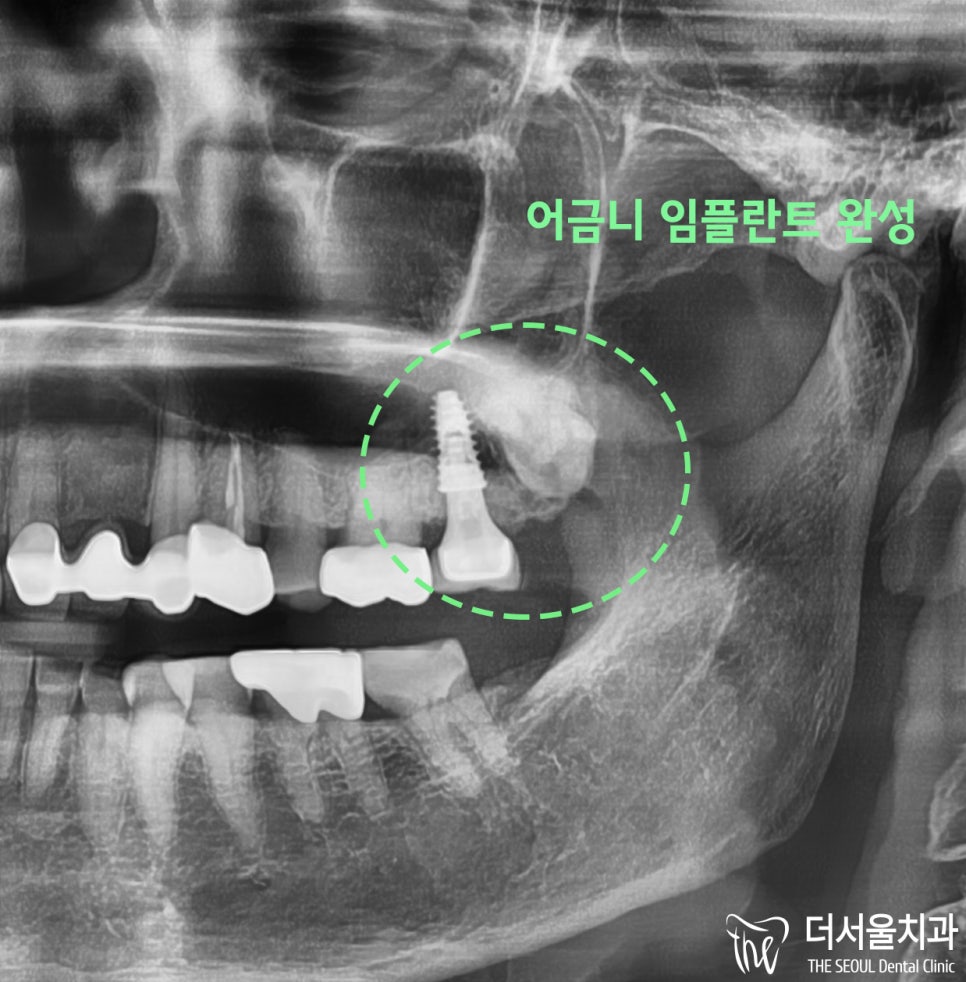

이를 바탕으로

어금니 임플란트를 식립하게 되었고

적절한 골융합을 거쳐서 보철을 올려드렸습니다.

완성된 사진을 보여드리겠습니다.

사랑니를 건드리지 않고

#27번 어금니 부위에 임플란트를 심었습니다.

(정말 깔끔하죠-?!)